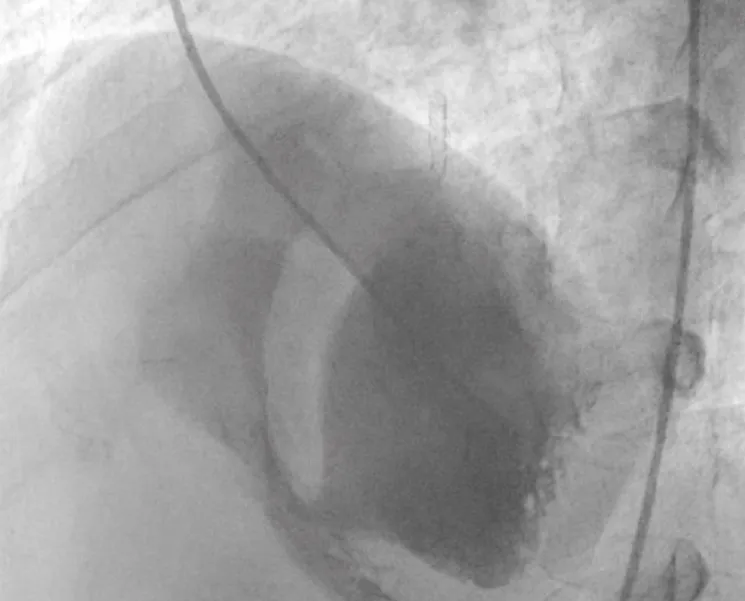

The technique of percutaneous closure of a VSR is based upon the well-proven and widely accepted percutaneous congenital ventricular septal defect closure. Transthoracic echocardiography (TTE) with colour Doppler was used to determine the size and anatomy of the VSR in all cases (Figure 1).

Figure 1: Transthoracic echocardiography (TTE) with colour Doppler to determine the size and anatomy of the VSR.